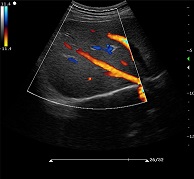

? ?● 多種成像模式

? ? ? ?B、C、PW、CW、BCD三功、大角度偏轉(zhuǎn)成像、實(shí)時(shí)寬景成像、梯形成像(僅支持線陣)、解剖M型、彩色M型成像、組織多普勒成像、3D/4D成像

? ?● 彩色多普勒增強(qiáng)技術(shù)

? ? ? ?有效抑制彩色血流閃動(dòng)噪聲,提高血流分辨率和靈敏度